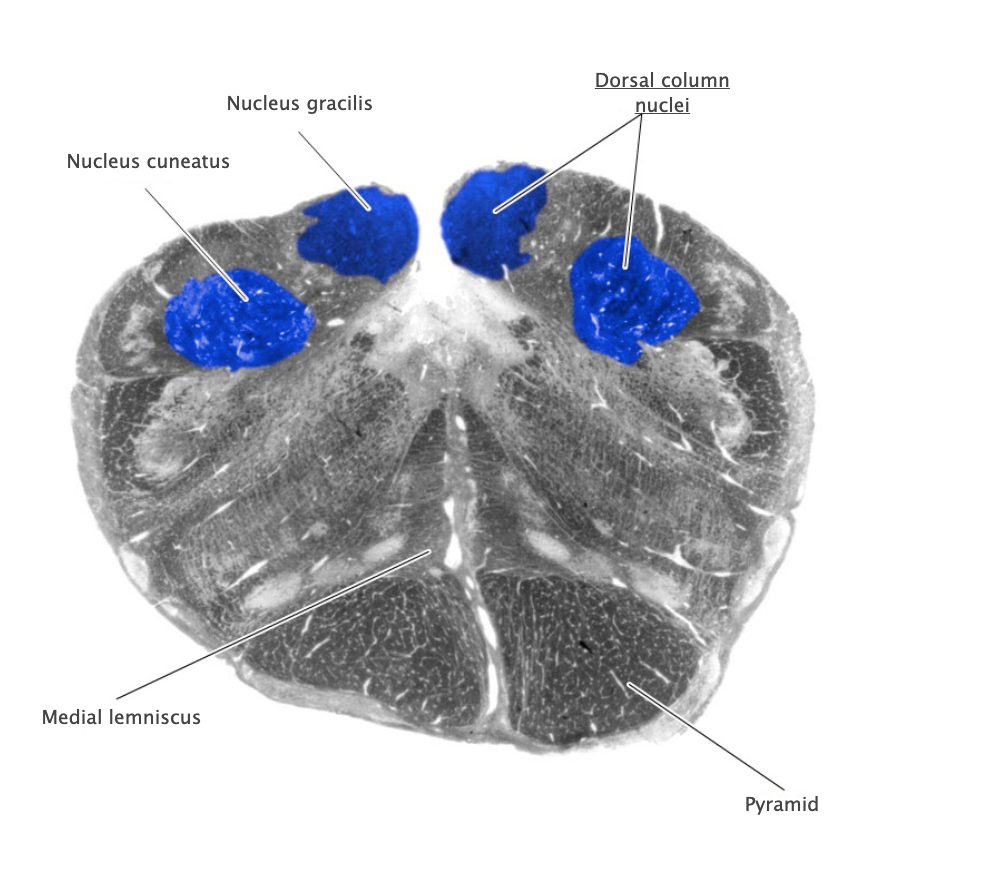

Dorsal column nuclei

Gracile nucleus and cuneate nucleus; contain the second-order sensory neurons that relay mechanosensory information from peripheral receptors in the body (excluding the face) to the thalamus via the medial lemniscus. The dorsal column nuclei are located in the lower medulla.

Nucleus cuneatus

Dorsal column nucleus in the lower medulla; contains second-order sensory neurons that relay mechanosensory information from peripheral receptors in the upper extremities to the thalamus via the medial lemniscus.

Nucleus gracilis

Nucleus containing the second-order sensory neurons that relay mechanosensory information from peripheral receptors in the lower body to the thalamus via the medial lemniscus, located in the lower medulla (also called the "gracile nucleus"). The nucleus gracilis also relays visceral pain information from second-order neurons in the central spinal cord to the thalamus.